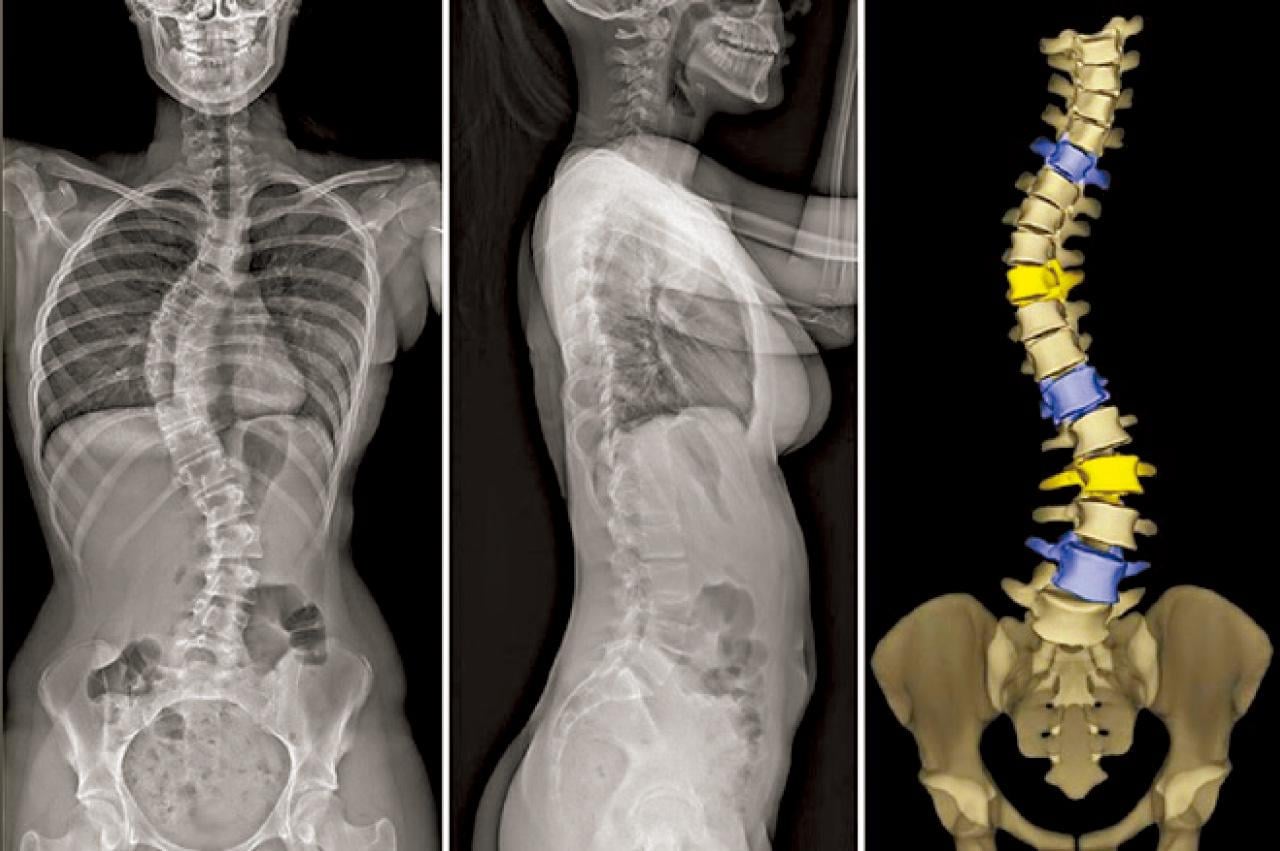

我在接受骨科訓練的時候,見到的多是較嚴重的患者。現在青少年可定期參加衛生署學童保健服務中的脊柱檢查,及早發現和治療。懷疑患上脊柱側彎的青少年大多會透過外表觀察和X光檢查作出評估和診斷。傳統X光檢查最少需要進行兩次或以上的掃描才可以覆蓋上半身至盤骨位置。除此之外,脊椎會隨著側彎而出現椎體旋轉的情況,醫生或難以單憑2D影像作出精準診斷。

較新的影像診斷叫「微劑量2D/3D X光醫學影像系統」(EOS)。EOS的輻射劑量比傳統X光銳減90%以上,只需一次掃描就可以覆蓋全身,患者毋須因重複掃描而接受額外輻射劑量,檢查快、準確度高。系統輸出的影像沒有傳統X光影像失真的缺點,誤差率低;經軟件自動進行分析和重建3D影像,有助醫生準確評估患者情況,以制訂適切的治療方案。最新的儀器還可以在掃描期間根據青少年的身體結構,自動調節輻射劑量,進一步減低輻射劑量。